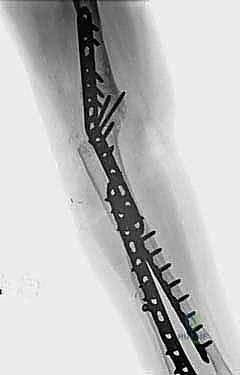

وهو جوهر العملية. يجب تثبيت العظام معاً بقوة هائلة حتى يكتمل الالتئام الذي قد يستغرق أشهراً. يستخدم الأستاذ الدكتور محمد هطيف أحدث التقنيات العالمية في هذا المجال:

* الشرائح والمسامير التيتانيوم: يتم وضع شريحة معدنية قوية (أو شريحتين متقاطعتين) تمتد من عظمة العضد إلى عظمة الزند لتثبيت المفصل بقوة.

* المسامير النخاعية: في بعض الحالات يتم إدخال مسمار طويل داخل تجويف العظام.

الخطوة الرابعة: الإغلاق والجبيرة

بعد التأكد من قوة التثبيت والزاوية المثالية عبر الأشعة السينية داخل غرفة العمليات، يتم إغلاق الجرح طبقة بطبقة، ووضع درنقة (أنبوب صغير) لسحب أي دم متجمع، ثم توضع الذراع في جبيرة قوية لحمايتها.